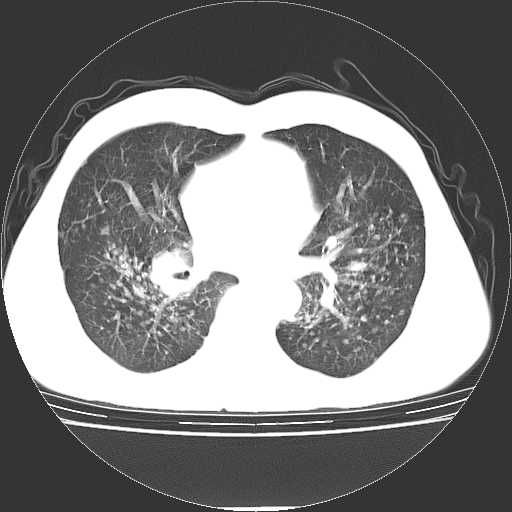

以下是引用yangyudong333在2008-4-29 5:38:00的发言:[br]比较典型的矽肺结节.支持[br]诊断依据:[br] 1.x线表现:[br] ①典型矽肺为多发直径 1~3mm 小结节,即矽结节,由胶原纤维和硅尘构成,可融合成团块,好发于上肺。[br] ②团块周围常有肺大泡。[br] ③胸内淋巴结增大、钙化。如肺门淋巴结呈蛋壳样钙化有助于与其他尘肺区别。[br] ④胸膜常广泛粘连、增厚。[br] 2.ct表现[br] ①两肺散在大小较为一致的小结节影,其密度较高,边界清楚。[br] ②小结节可融合为较大团块影,直径约 1cm ,甚至可达 10cm以上,易发生在上叶。[br] ③小结节周围常并有小叶中心气肿或弥漫性肺气肿。

以下是引用liuyue在2008-4-28 22:30:00的发言:[br]比较典型的矽肺结节.[br]请结合临床及化验除外矽肺合并肺结核之可能.